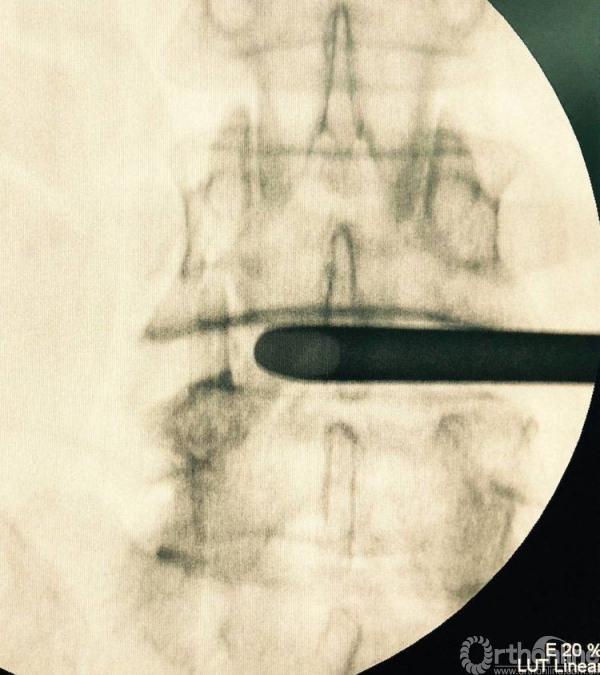

术前透视标记出棘突椎板关节突关节、椎弓根、横突复合体螺钉进钉路线的正位透视片

正位观察透视,判断是否处理至边缘

12号试模决定融合器大小

充分植骨(关节成型时的自体骨质、也可配合异体骨使用),然后植入融合器,镜下观察融合器和硬膜囊位置并透视再次确认

正侧位透视观察滑脱是否复位、融合器及植骨的位置